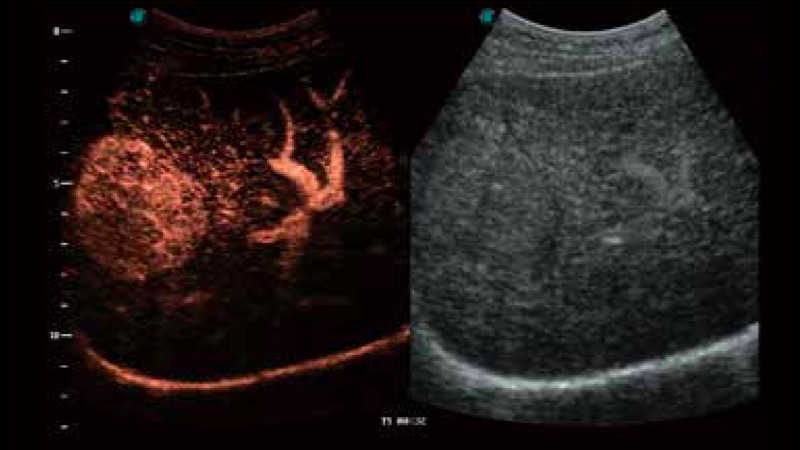

SR Flow高分辨率血流成像

高分辨率血流成像技术提高了对低速血流信号的检测能力。在提高空间分辨率的同时,也克服了血流外溢现象,为用户提供更加真实的血流动力学信息。

S-Live 高分辨率容积成像

通过仿真成像技术对3D/4D立体数据进行渲染,多种初始光源位置可选,并支持轨迹球360°光源位置自由调节,清晰显示不同方位容积图像细节。